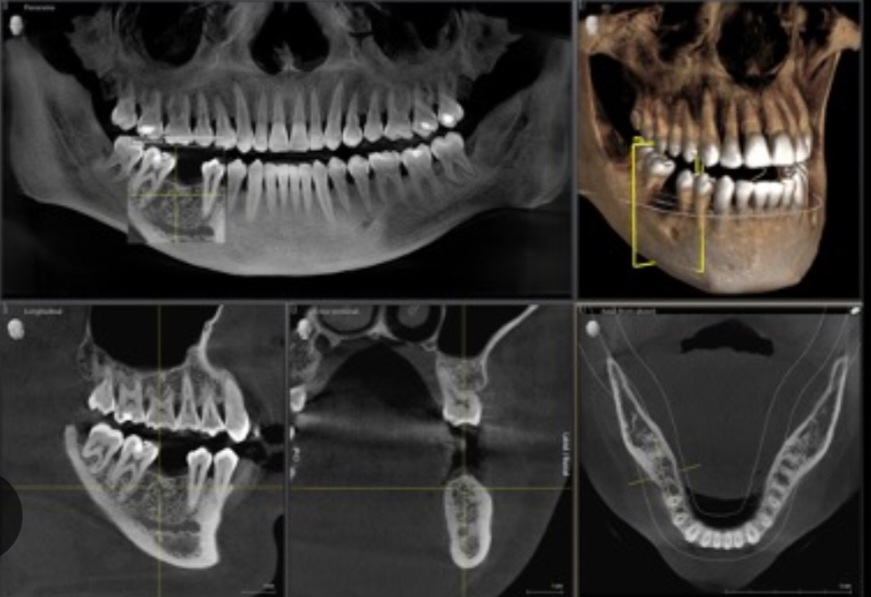

3D snimanje – CBCT ( Cone Beam Computerised Tomography)

CBCT snimanje predstavlja najsavremeniju dentalnu dijagnostičku metodu. Savremenim 3D – CBCT aparatima dobijamo rendgenske snimke izuzetne preciznosti i oštrine u sve 3 ravni projekcije. Pametni softveri nam omogućuju da te snimke dalje obradjujemo, merimo, analiziramo, pravimo planove i projekte koji su često od presudnog dijagnostičkog i terapijskog značaja.

Samo jednim 3D snimkom lako možemo dobiti detaljne prikaze kompletne vilice, zuba, viličnih zglobova, maksilarnih sinusa i svih ostalih okolnih koštanih struktura. CBCT snimci se najčešće koriste u oralnoj i maksilofacijalnoj hirurgiji, implantologiji, endodonciji, ortodonciji, a sve češće i u drugim granama stomatologije i medicine.

Najveća prednost CBCT-a je što se samo jednim snimanjem dobija ogroman broj visokokvalitetnih snimaka koji su u dijagnostičkom smislu neprocenljivi. Zbog svih benefita koje ima, 3D snimanje je postalo izuzetno moćno i dominantno dijagnostičko sredstvo. Svugde u svetu, pa tako i kod nas, moderna stomatologija se više ne može zamisliti bez 3D – CBCT snimanja.